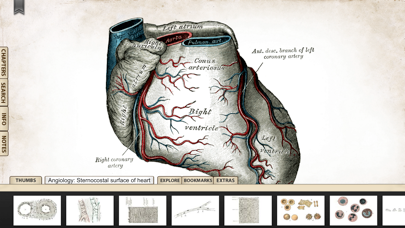

1. 'Gray's Anatomy', the renowned classic anatomical book by Henry Gray was first published in 1858 and is considered by many to be one of the most iconic and significant medical books of all time.

2. Gray's Anatomy is now available on the iPhone and iPod Touch using the highest resolution images possible.

6. We recommend this app for Doctors, Nurses, Students, Teachers and anyone who is interested in the wonder and complexity of the human body.